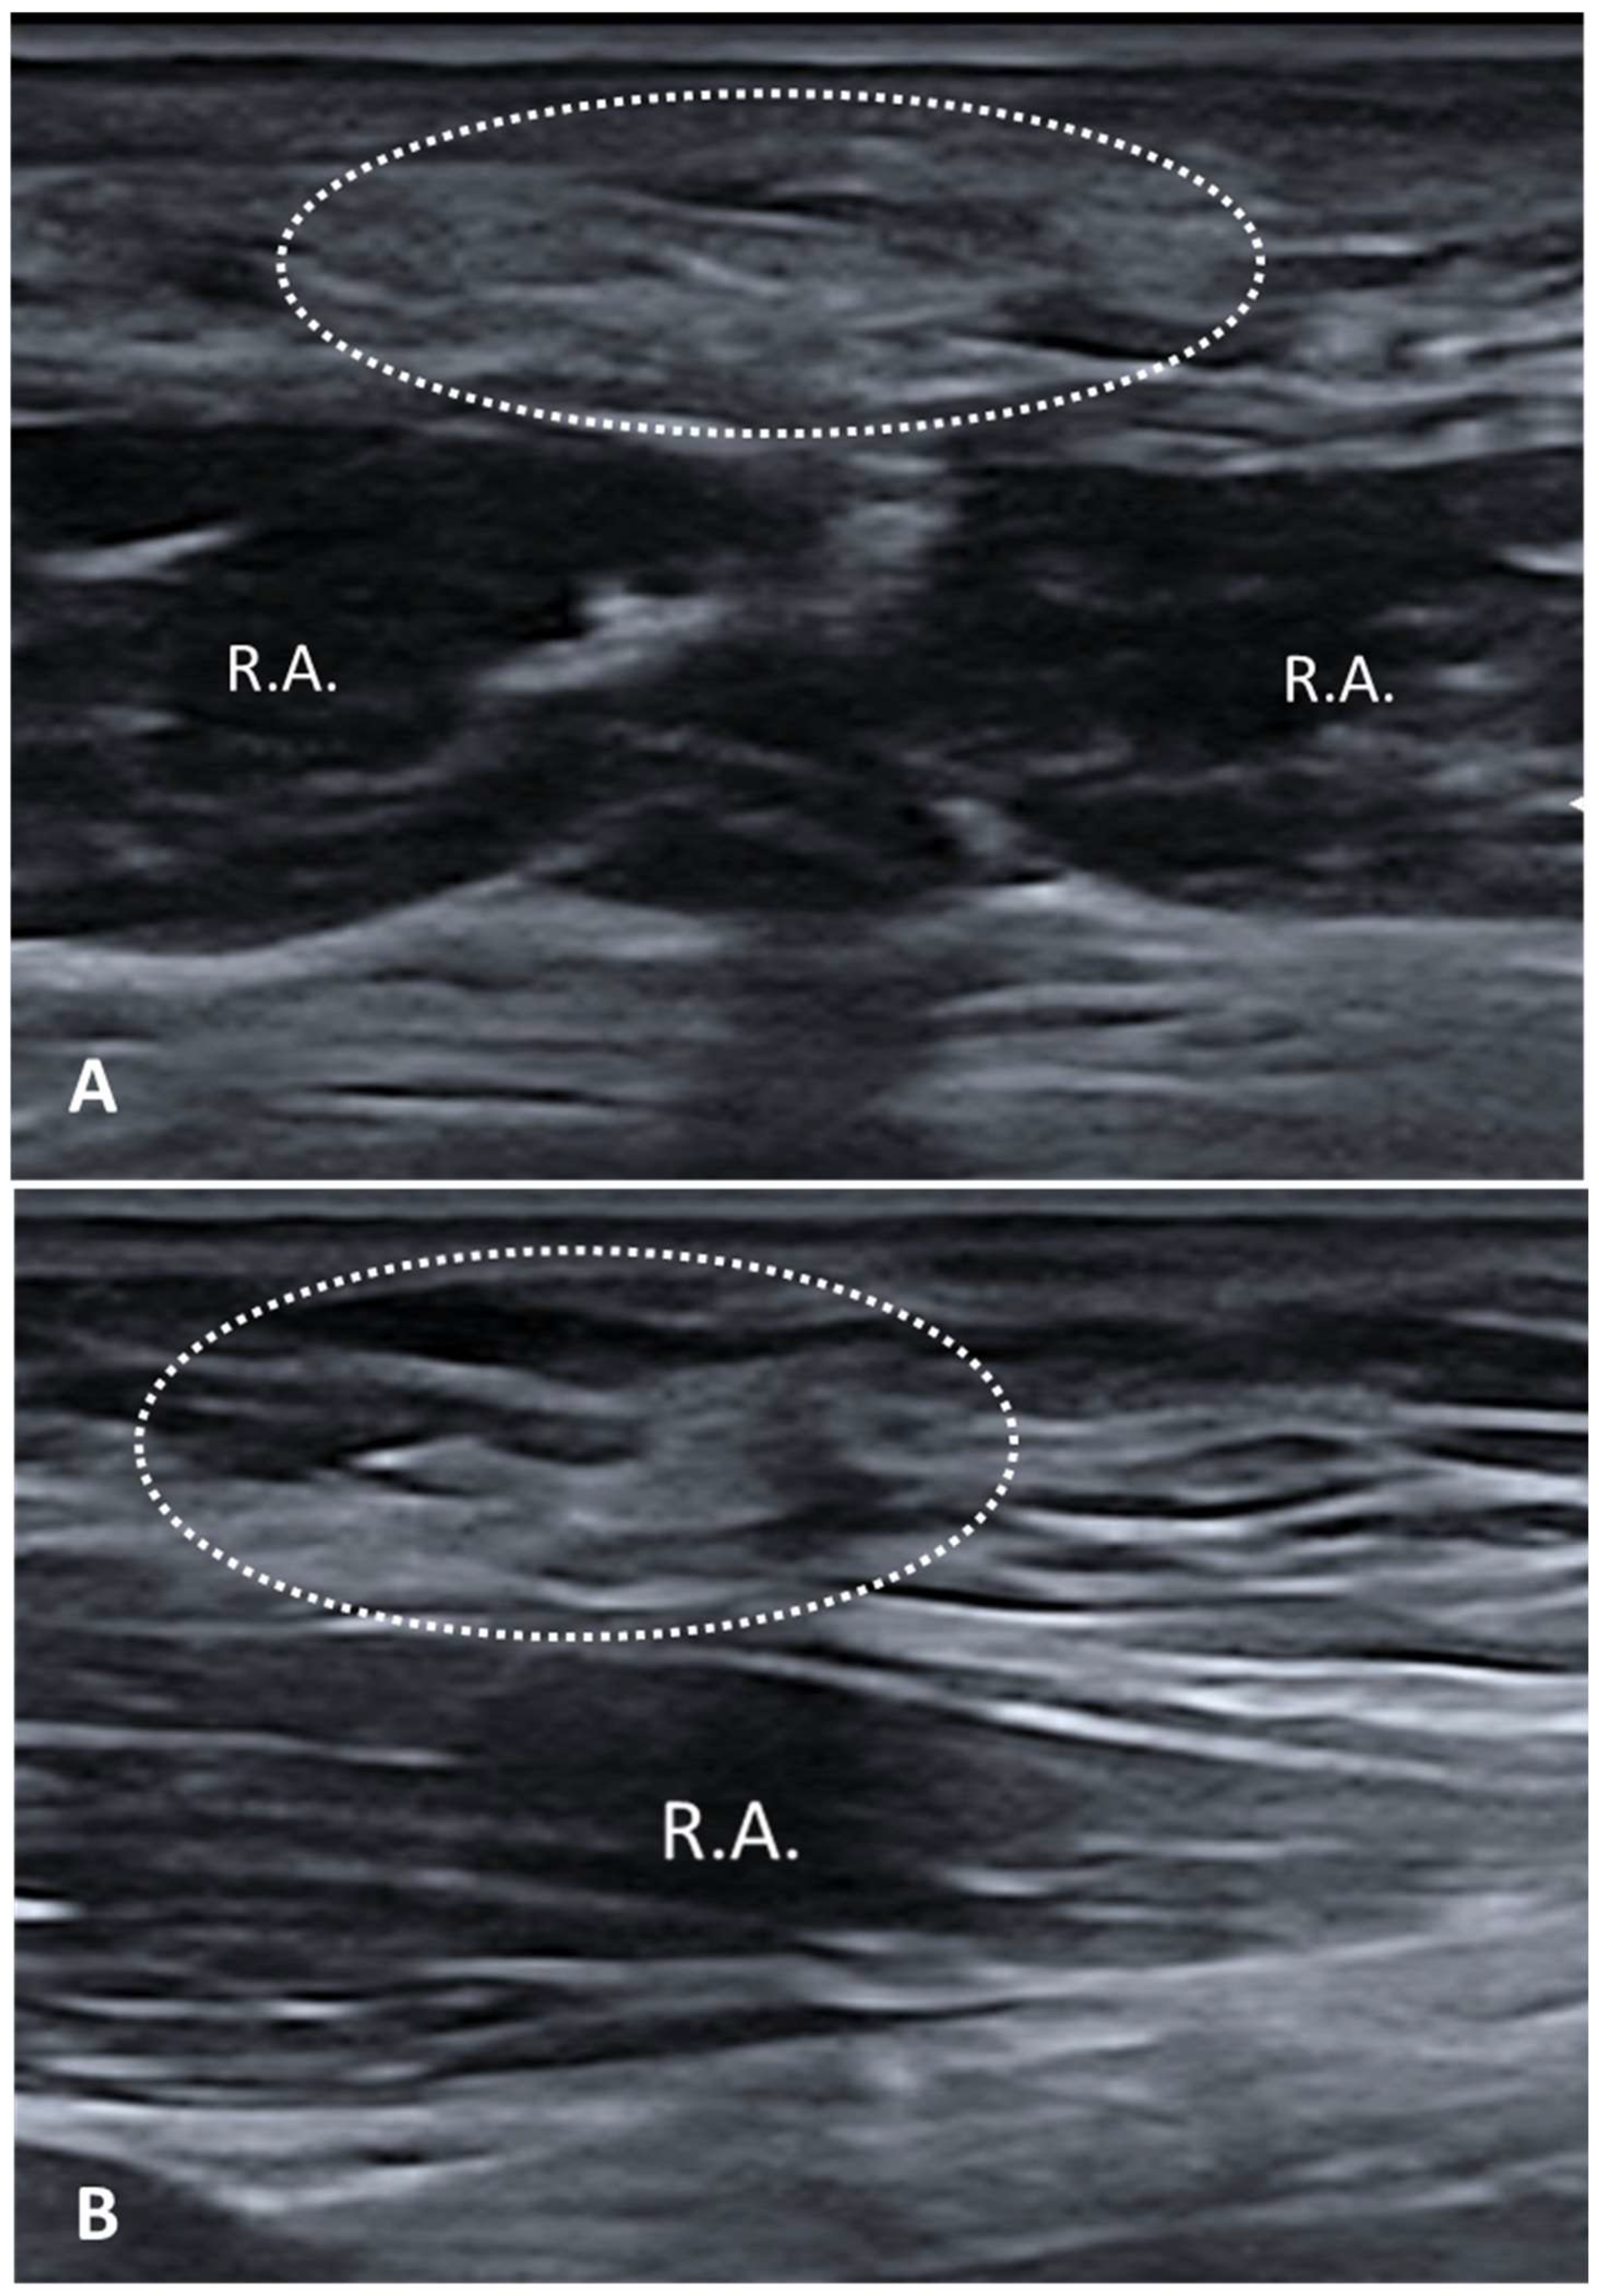

- Fan, C.; Guidolin, D.; Ragazzo, S.; Fede, C.; Pirri, C.; Gaudreault, N.; Porzionato, A.; Macchi, V.; De Caro, R.; Stecco, C. Effects of Cesarean Section and Vaginal Delivery on Abdominal Muscles and Fasciae. Medicina 2020, 56, 260. [Google Scholar] [CrossRef] [PubMed] [PubMed Central]